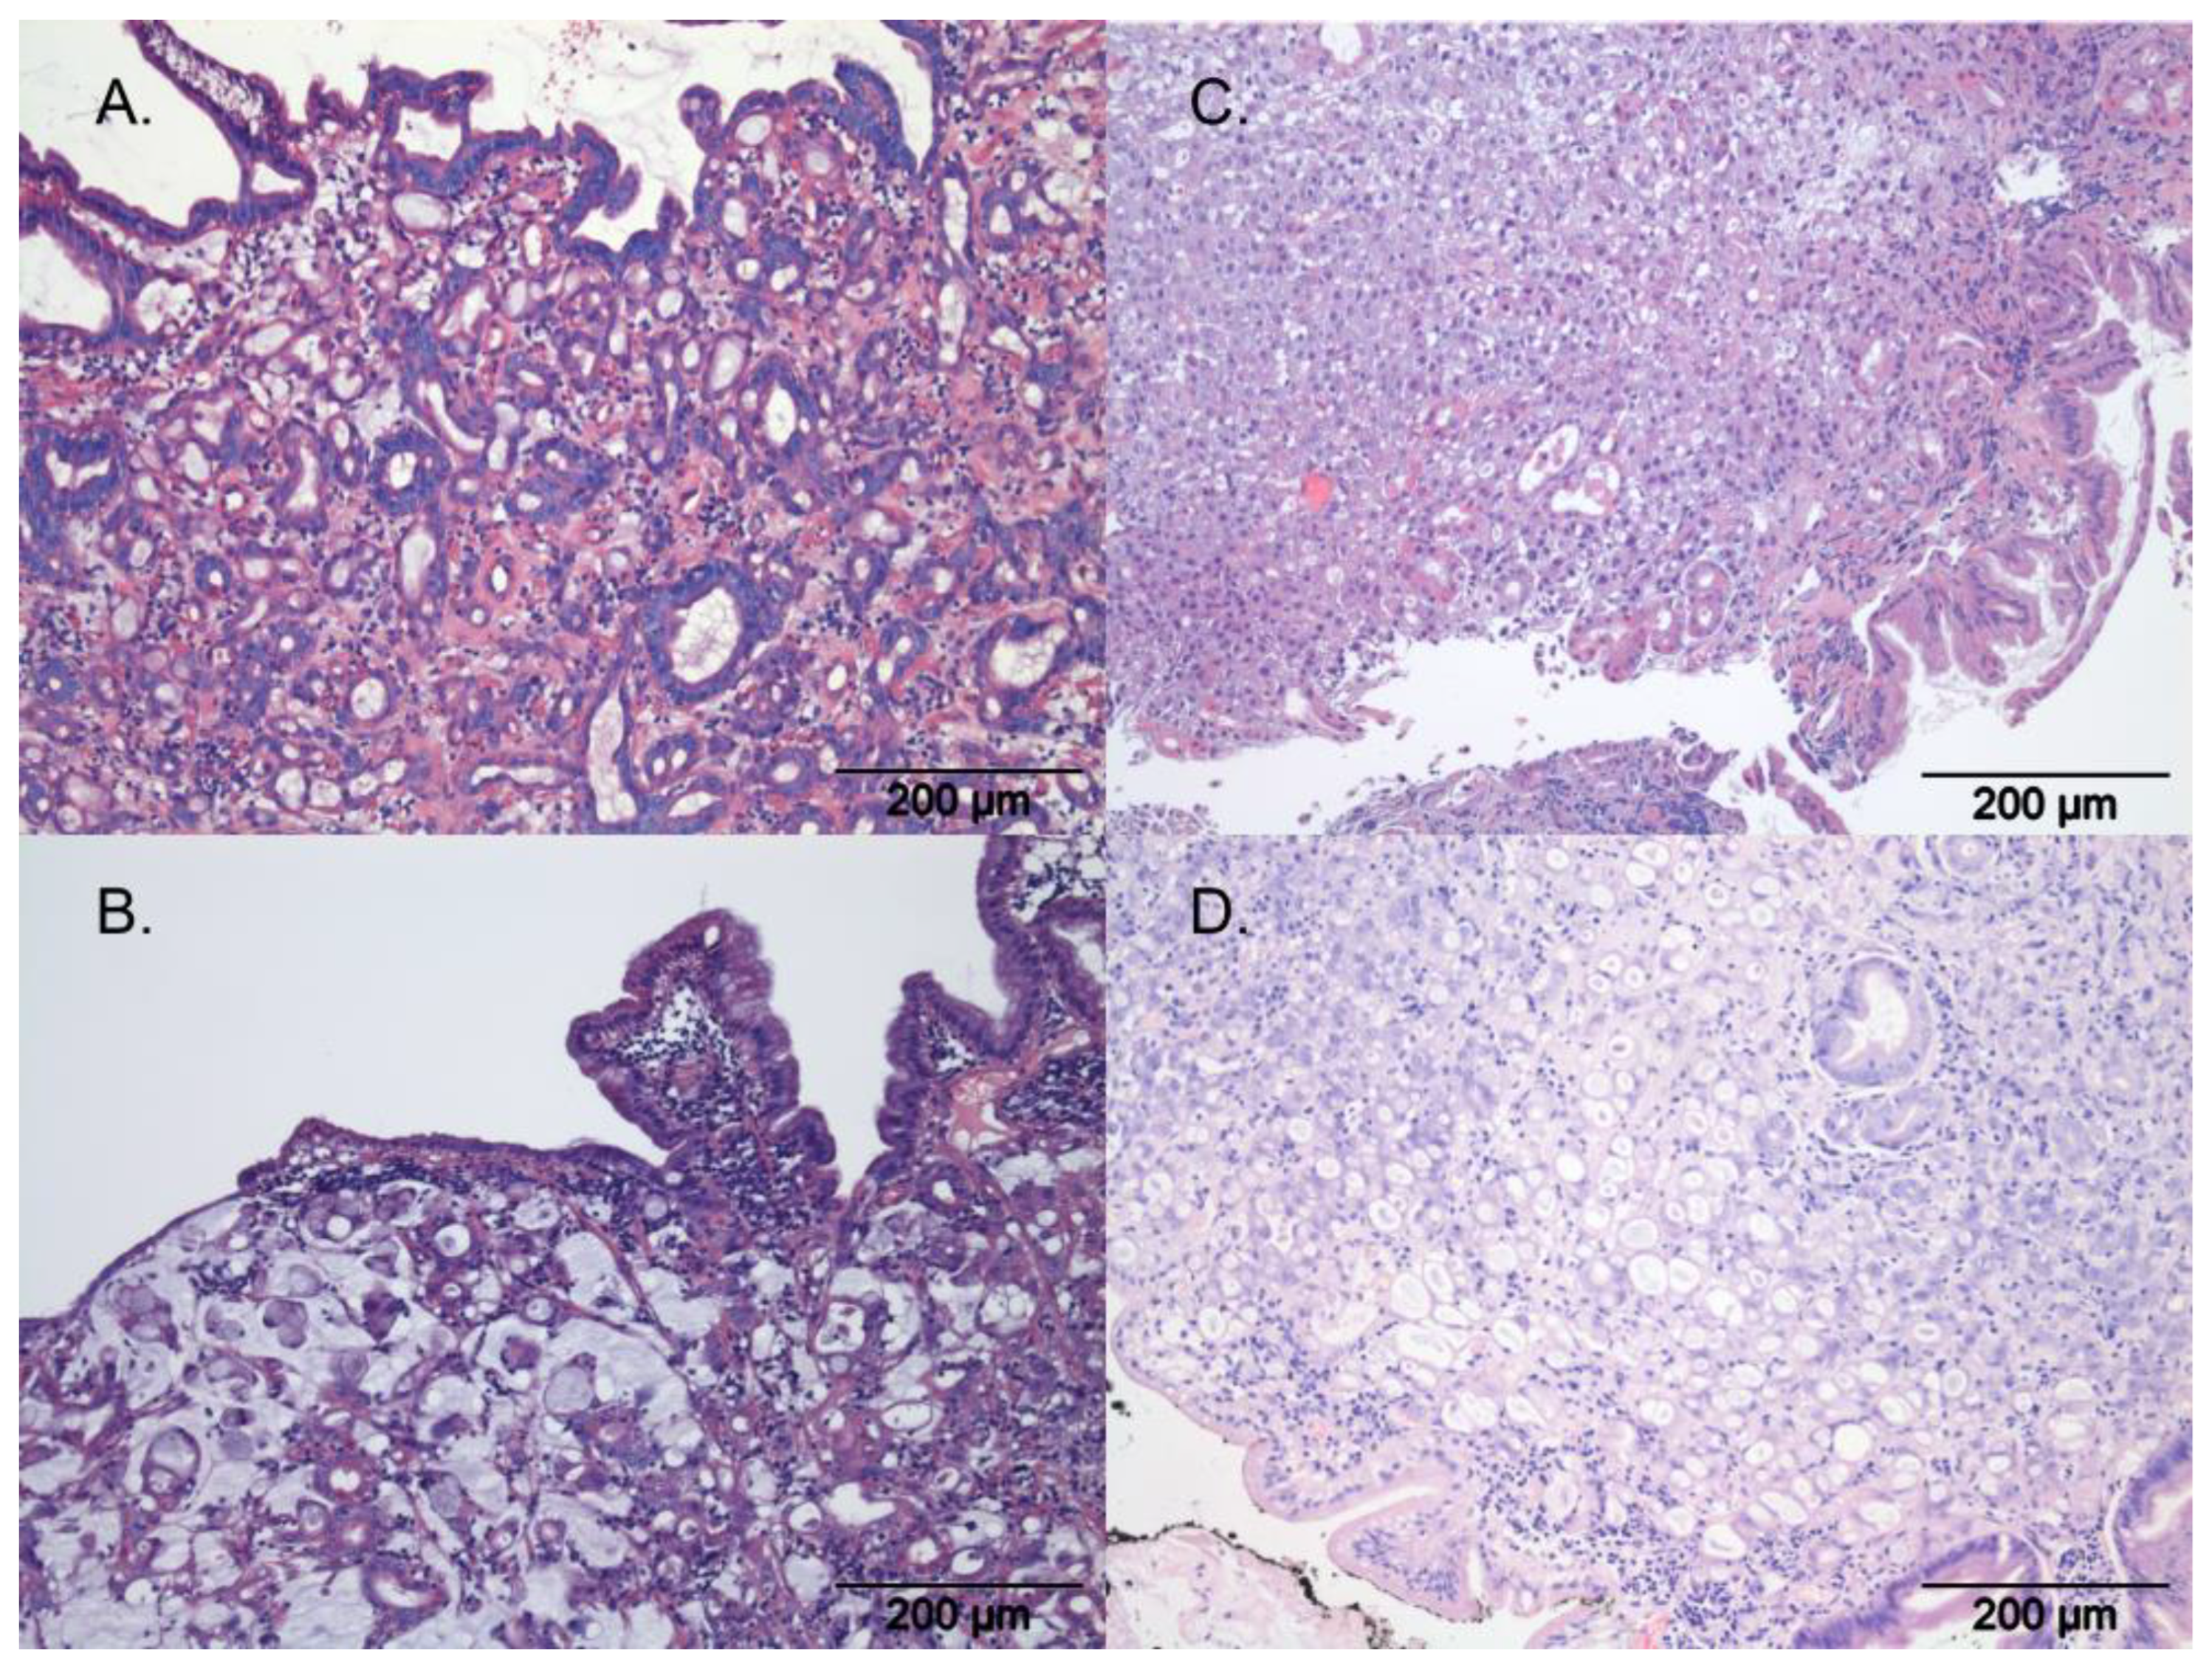

3.2. Tumour Classification and Pathology